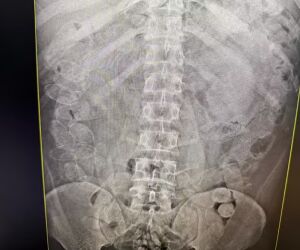

Diante da suspeita de que os demais homens pudessem ter ingerido a droga, os quatro foram encaminhados para um hospital da cidade, onde passaram por exames de raio X.

Um deles afirmou que não conseguiu engolir as cápsulas e que todo o material encontrado com ele era de sua responsabilidade. Já os outros três confessaram ter engolido cerca de 86 cápsulas cada um.